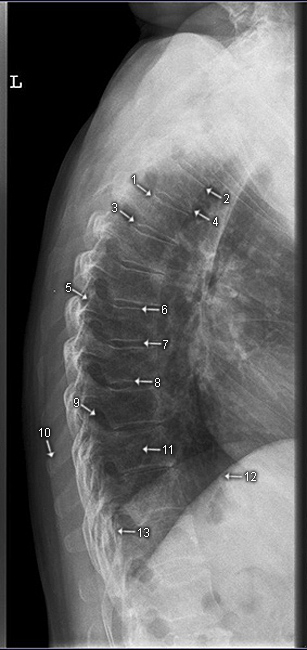

HWS seitlich

1. Basis cranii (Schädelbasis)

2. Arcus posterior (hinterer Atlasbogen)

3. Arcus anterior (vorderer Atlasbogen)

4. Dens axis

5. Processus spinosus

6. Mandibula

7. Corpus axis

8. vordere obere Wirbelkörperkante

9. Processus articularis superior

10. Processus transversus

11. Processus articularis inferior

12. vordere untere Wirbelkörperkante

13. Wirbelkörperdeckplatte

14. Intervertebralgelenk (= kleines Wirbelgelenk)

15. Arkus

16. Proc. spinosus (vertebrae prominentis)

17. Gelenkpfeiler

18. Wirbelkörpergrundplatte

19. Zwischenwirbelraum